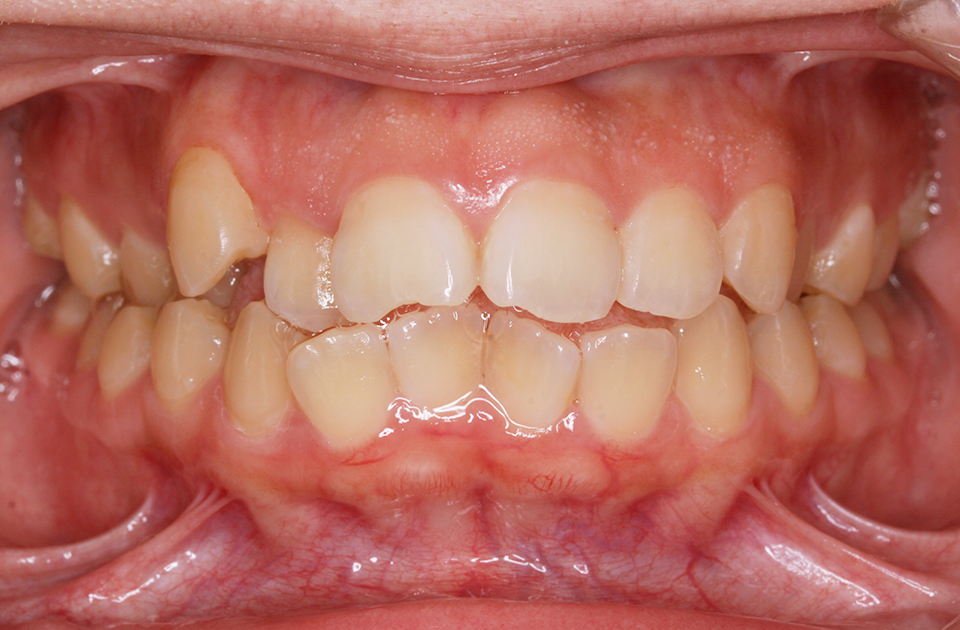

矯正前 正面

矯正後 正面

主訴 前突感、口が閉じずらく前歯で物が咬めない。

年齢 20代

治療法 上下顎マルチブラケット装置

抜歯の有無 上顎左右側第一小臼歯、下顎左右側第一小臼歯

治療期間 1年10ヶ月